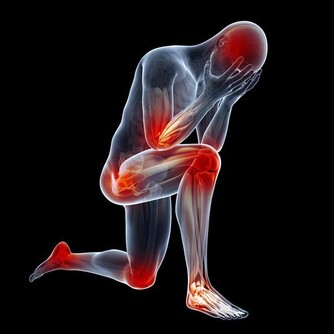

❶、【功能與主治】散瘀止血,消腫定痛。用於咯血,吐血,衄血,便血,崩漏,外傷出血,胸腹刺痛,跌撲腫痛。 ❷、【食用功效】有益氣養血、治療崩漏、產後虛弱、自汗、盜汗、有滋陽強壯作用。也治療老年人的頭風痛、腰肌痠軟無力等症。 廣告 - 請繼續往下閱讀 3枸杞

❶、【功能與主治】:滋補肝腎,益精明目。用於虛勞精虧,腰膝痠痛,眩暈耳鳴,內熱消渴,血虛萎黃,目昏不明。 4黃芪

廣告 - 請繼續往下閱讀 ❶ 、【功能與主治】補血活血,調經止痛、潤腸通便。用於血虛萎黃,眩暈心悸,月經不調,經閉痛經,虛寒腹痛,腸燥便秘,風濕痺痛,跌撲損傷,癰疽瘡瘍。酒當歸活血通經。用於經閉痛經,風濕痺痛,跌撲損傷。 7天麻

天麻天麻潤而不燥,主入肝經,長於平肝息風,凡肝風內動、頭目眩暈之症,不論虛實,均為要藥。 ❶ 、平肝息風。天麻質潤多液,能養血息風,可治療血虛肝風內動的頭痛、眩暈,亦可用於小兒驚風、癲癇、破傷風。 ❷、祛風止痛。用於風痰引起的眩暈、偏正頭痛、肢體麻木、半身不遂。 廣告 - 請繼續往下閱讀 8南沙參